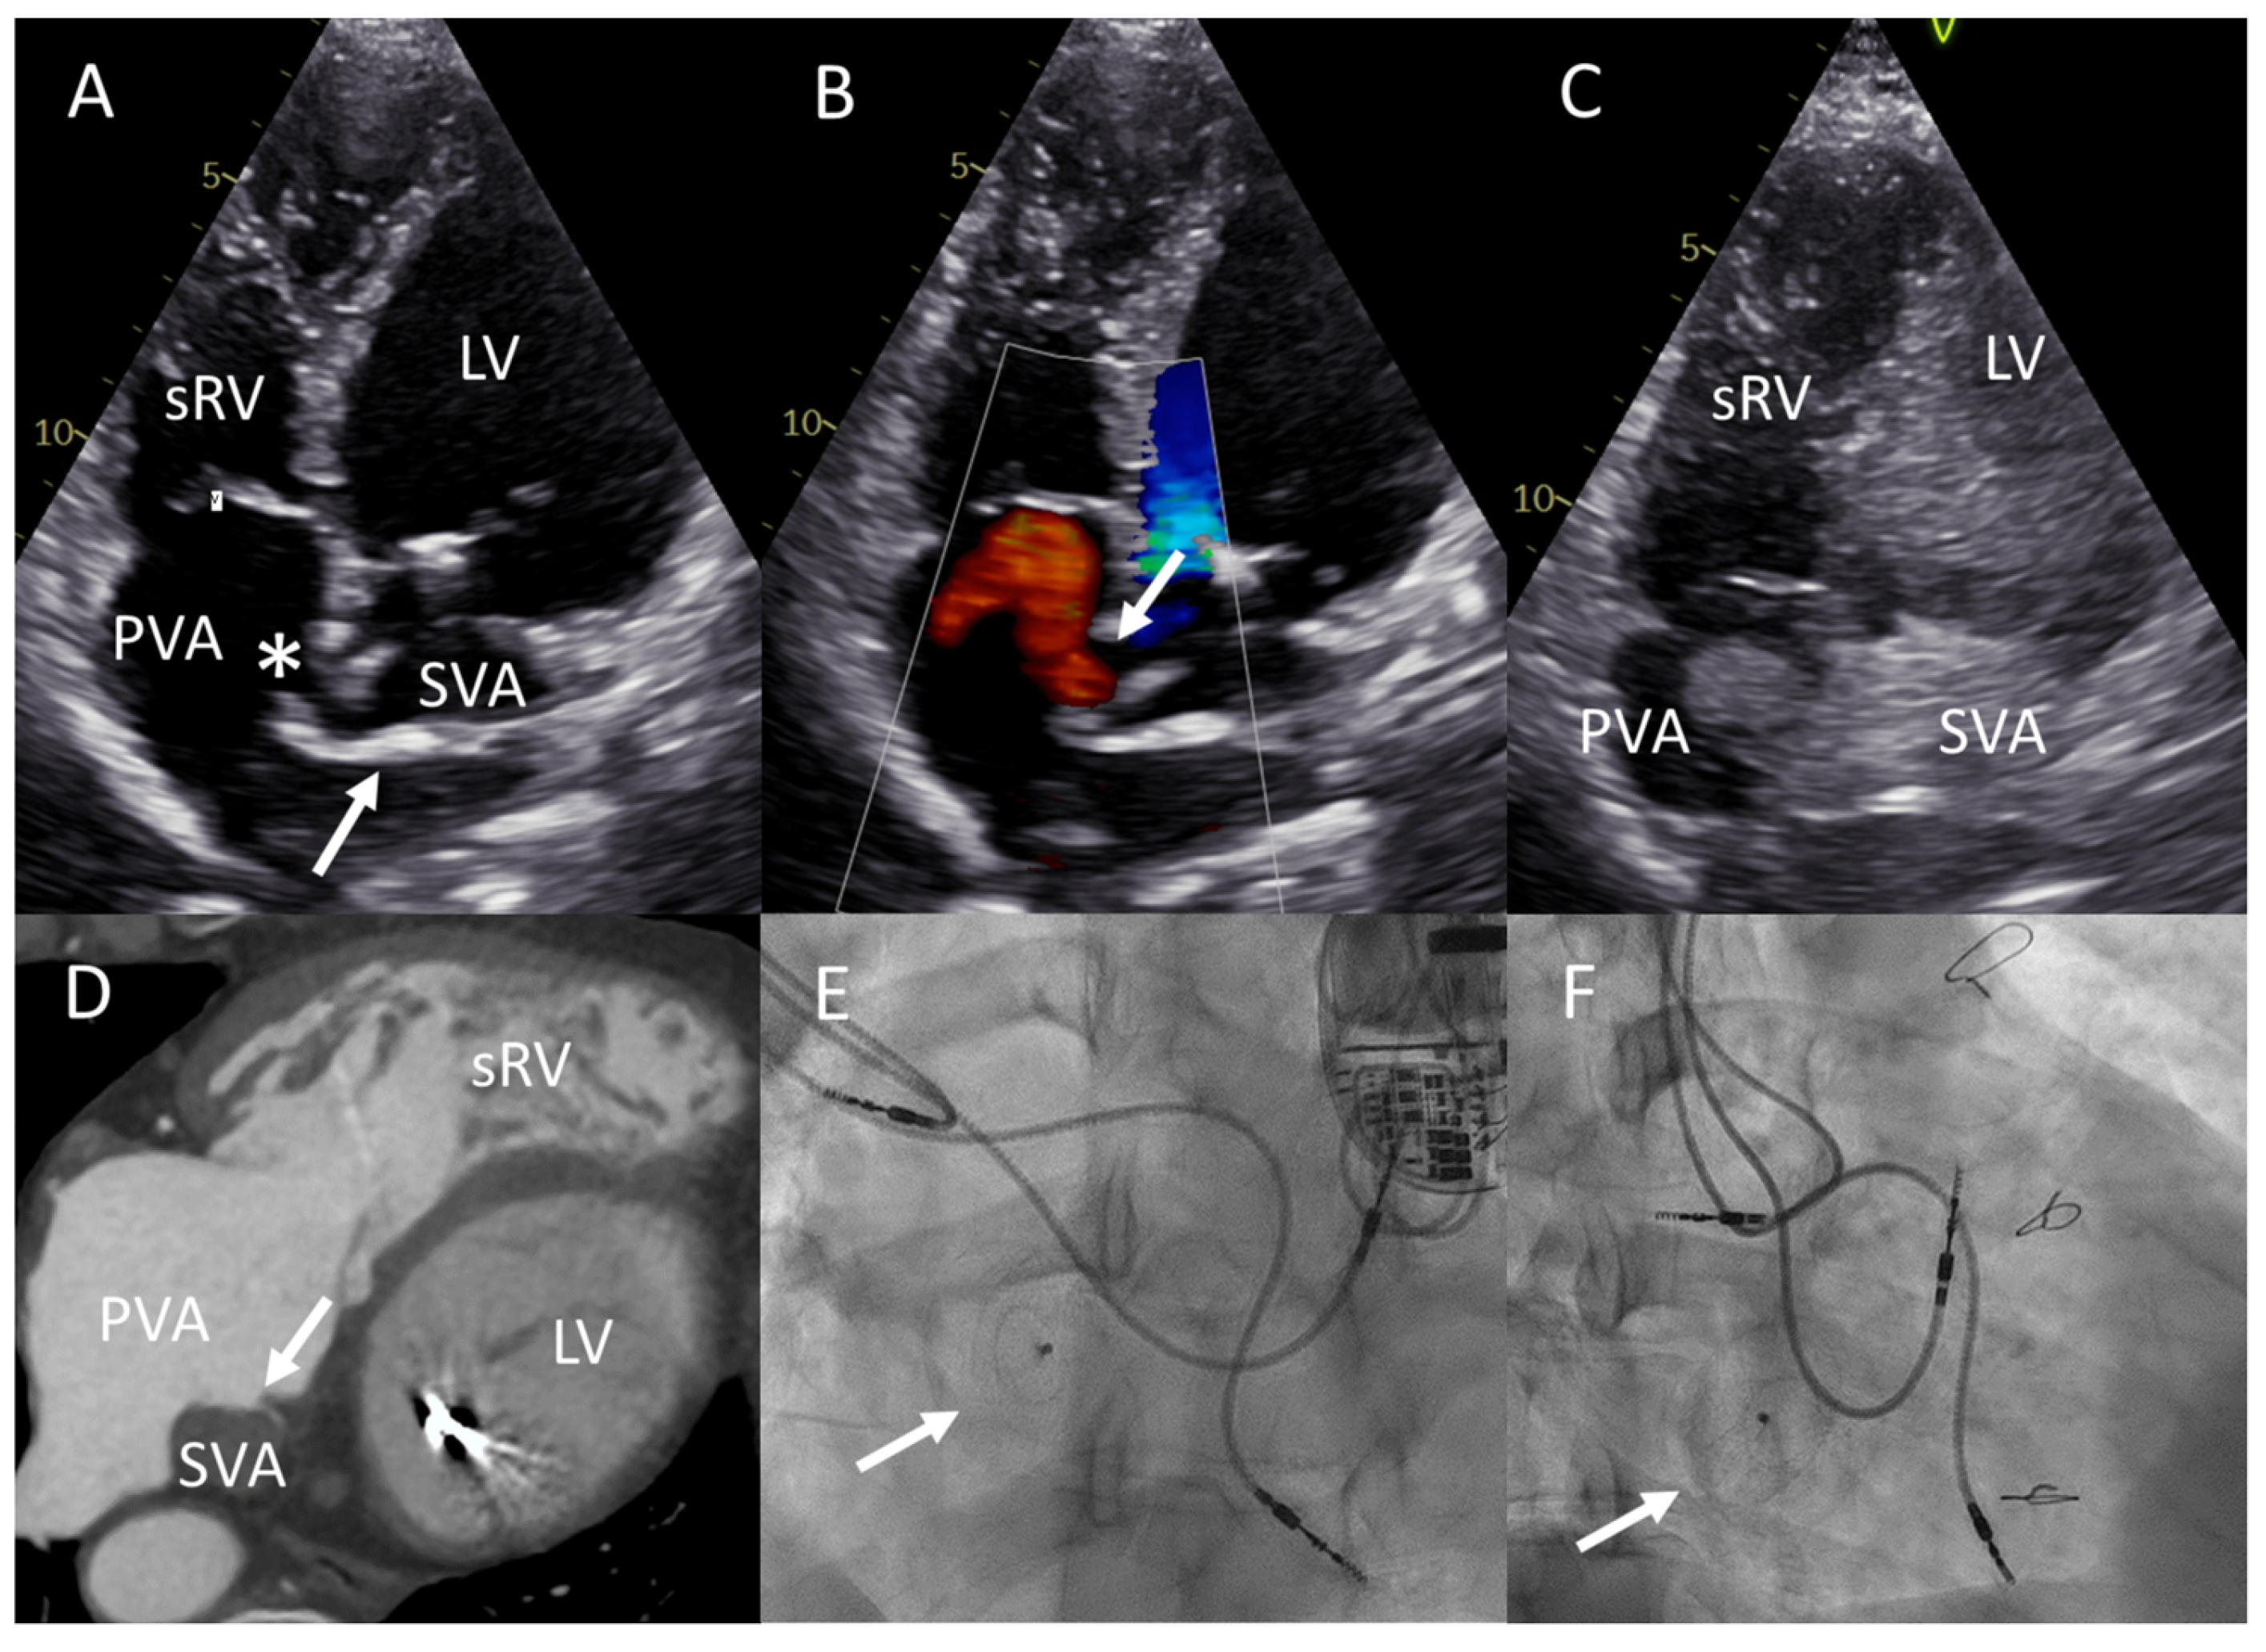

2.1. Patient A